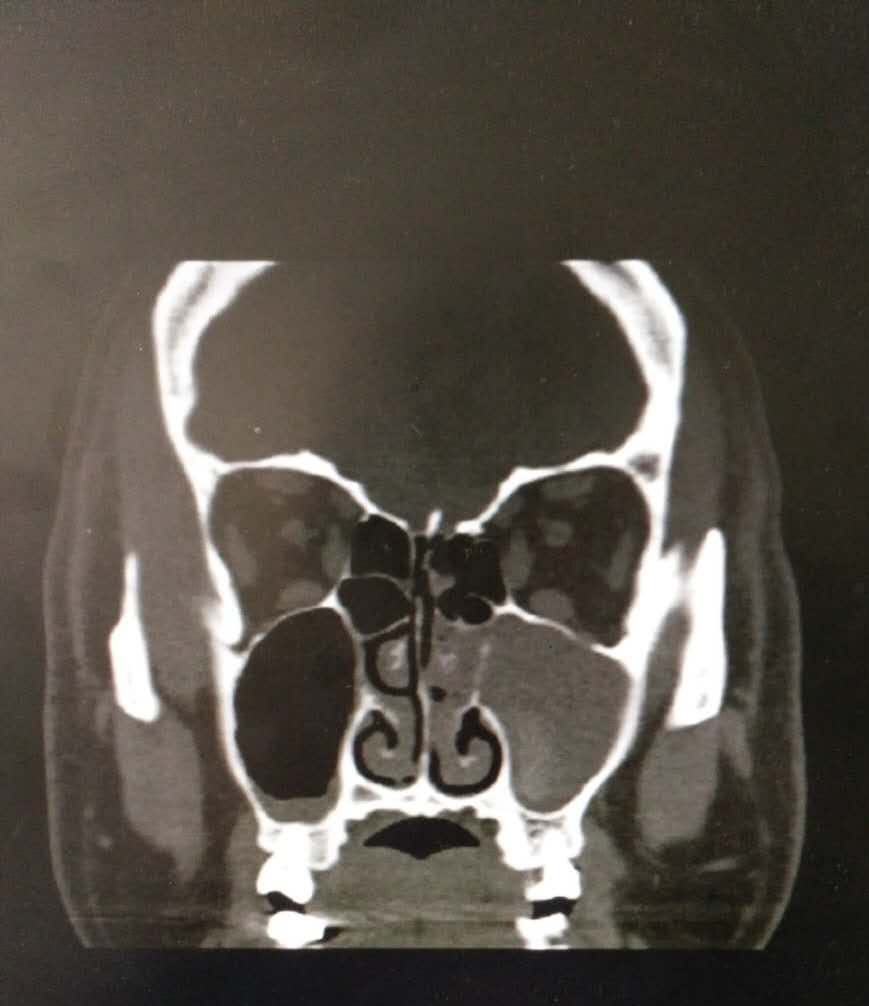

查体:鼻腔黏膜慢性充血,鼻腔内可见脓性分泌物,鼻中隔向左偏曲,双侧下鼻甲肥大。鼻内镜:双侧鼻腔可见脓性分泌物,鼻中隔左偏,进镜困难,似有中鼻道息肉,鼻咽部黏膜光滑,无新生物。鼻窦CT:双侧上颌窦、筛窦及鼻腔内炎症改变。

诊断:1.慢性鼻窦炎鼻息肉(左)2.鼻中隔偏曲 治疗:入院后完善检查,全麻下行导航鼻内镜下左侧上颌窦、筛窦开放术+鼻中隔矫正+双下甲骨折外移术。术中见左侧上颌窦内淡黄色光滑息肉样新生物,肿物根部位于底壁。